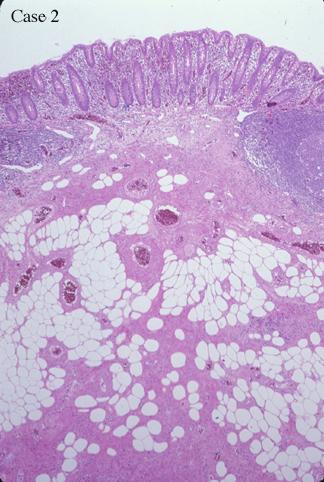

疾患(病理主体)の分類良性非上皮性腫瘍/血管脂肪腫

検査方法ミクロ